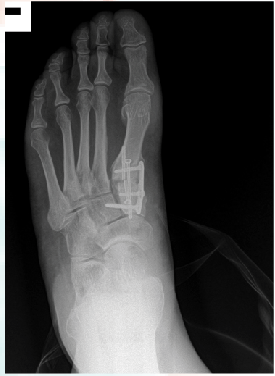

Therefore, most surgeons use common radiographic signs to rule out primary delay and eventual non-union. Some of these signs include the presence of a bridging callus, three of four cortices being bridged by callus formation and the resorption of fracture lines.2 Evaluation of the hardware across the proposed fusion site is also a good indicator. Hardware failure often indicates motion across the site with a lack of bony union, which places more force on the hardware, resulting in failure. Radiographic assessment is limited to the rate at which bony changes are visible in radiographs, which can take months.